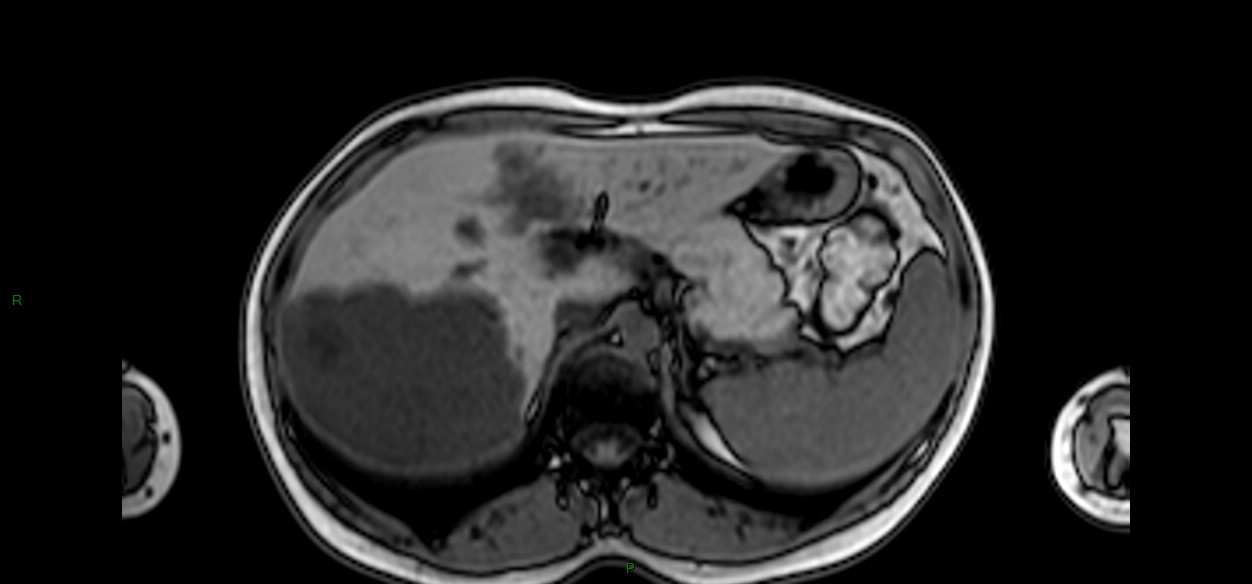

Cholangiocarcinome : cancer primitif des voies biliaires

Différentes formes de Cholangiocarcinome

Case courtesy of Ed Uthman, Radiopaedia.org. From the case rID: 8480